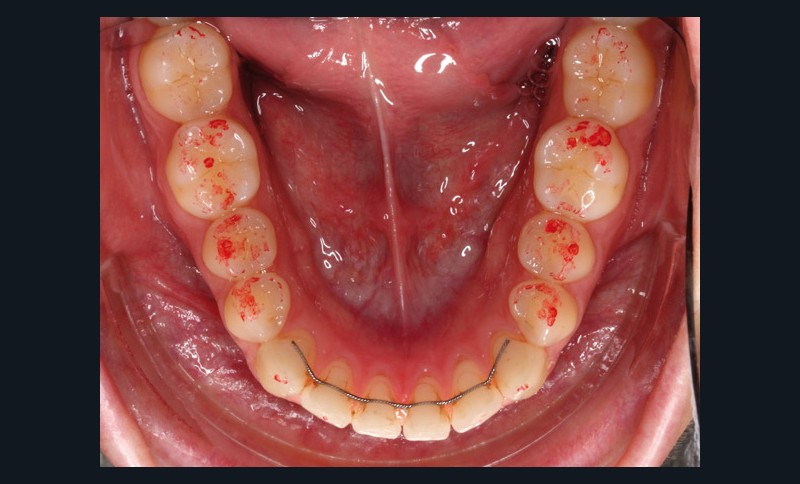

Ces différents aspects dépendent non seulement de la qualité et de l’épaisseur du papier, de son support, de la composition de l’encre, de l’imprégnation salivaire, mais aussi de la force de morsure [3-8]. En fonction du nombre de morsures et de la manière dont le patient serre sur le papier à articuler, la couleur, la taille et la forme des marques varient (fig. 1).

De plus, son utilisation répétée réduit significativement la précision et la sensibilité [4]. Même lorsque ces papiers sont employés dans des conditions idéales, les marques ne sont pas reproductibles [2-5, 9, 10] et le papier à articuler est souvent sujet à des perforations ou des déchirures lors des mouvements de fermeture en intercuspidie [9]. D’autre part, sur un champ humide, l’encre peut diffuser, ou le papier peut se plier, par exemple par retour du papier occlusal…